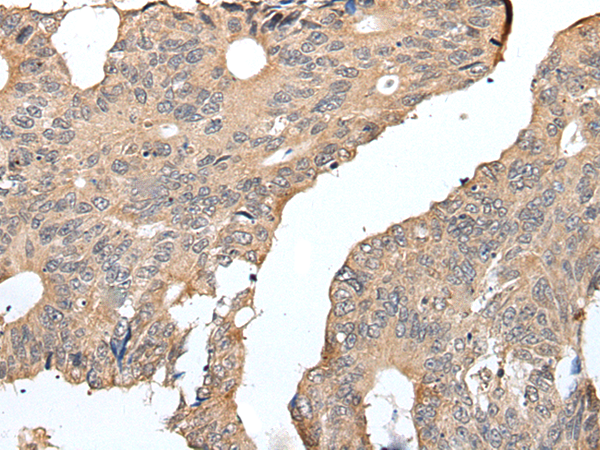

IHC positive control: |

Human colorectal cancer |

IHC Recommend dilution: |

25-100 |